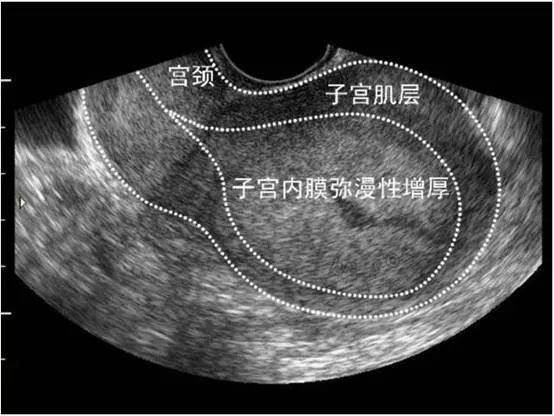

一般情况下,在月经结束后即刻超声检查,可以判断子宫内膜的厚度,太薄不好,太厚也不好。正常情况下子宫内膜厚度在5mm以下。随卵巢雌激素的刺激,内膜增厚,在排卵前8mm左右。排卵后卵巢分泌孕激素致内膜再增厚,月经来前14-16mm。个别女性朋友子宫内膜的厚度要稍微偏厚一点,属于正常的情况。

子宫内膜增厚

引起子宫内膜增厚的原因主要有:内源性雌激素、外源性雌激素

1.内源性雌激素所致:不排卵(青春期女孩、围绝经妇女、下丘脑-垂体-卵巢轴环节失调、多囊卵巢综合征等有不排卵现象,子宫内膜持续受雌激素作用)、肥胖(脂肪长期转化为雌激素)、内分泌功能性肿瘤(例如垂体腺的促性腺功能不正常,卵巢颗粒细胞瘤持续性分泌雌激素)

2.外源性雌激素所致:雌激素替代疗法(围绝经期或绝经后,雌激素缺乏、更年期综合征,合并有骨质疏松、血脂代谢异常等,长期口服含有雌激素的药物,会刺激子宫内膜增厚)、长期口服他莫昔芬药物也可使子宫内膜增生增厚。